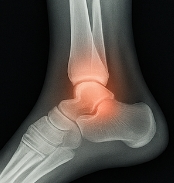

발목 접질렀을때 나타나는 주요 증상

발목 접질렀을때 다음과 같은 증상이 나타납니다.

- 통증: 발목 주변에 날카로운 통증이 즉시 발생.

- 붓기: 발목이 붓고 열감이 동반될 수 있습니다.

- 멍(피하출혈): 혈관이 손상되면 피부에 멍이 들 수 있습니다.

- 움직임 제한: 발목 접질렀을때 걷기 어렵거나 체중 부하 시 통증이 심해집니다.

이러한 증상은 발목 접질렀을때 손상의 정도에 따라 달라집니다.